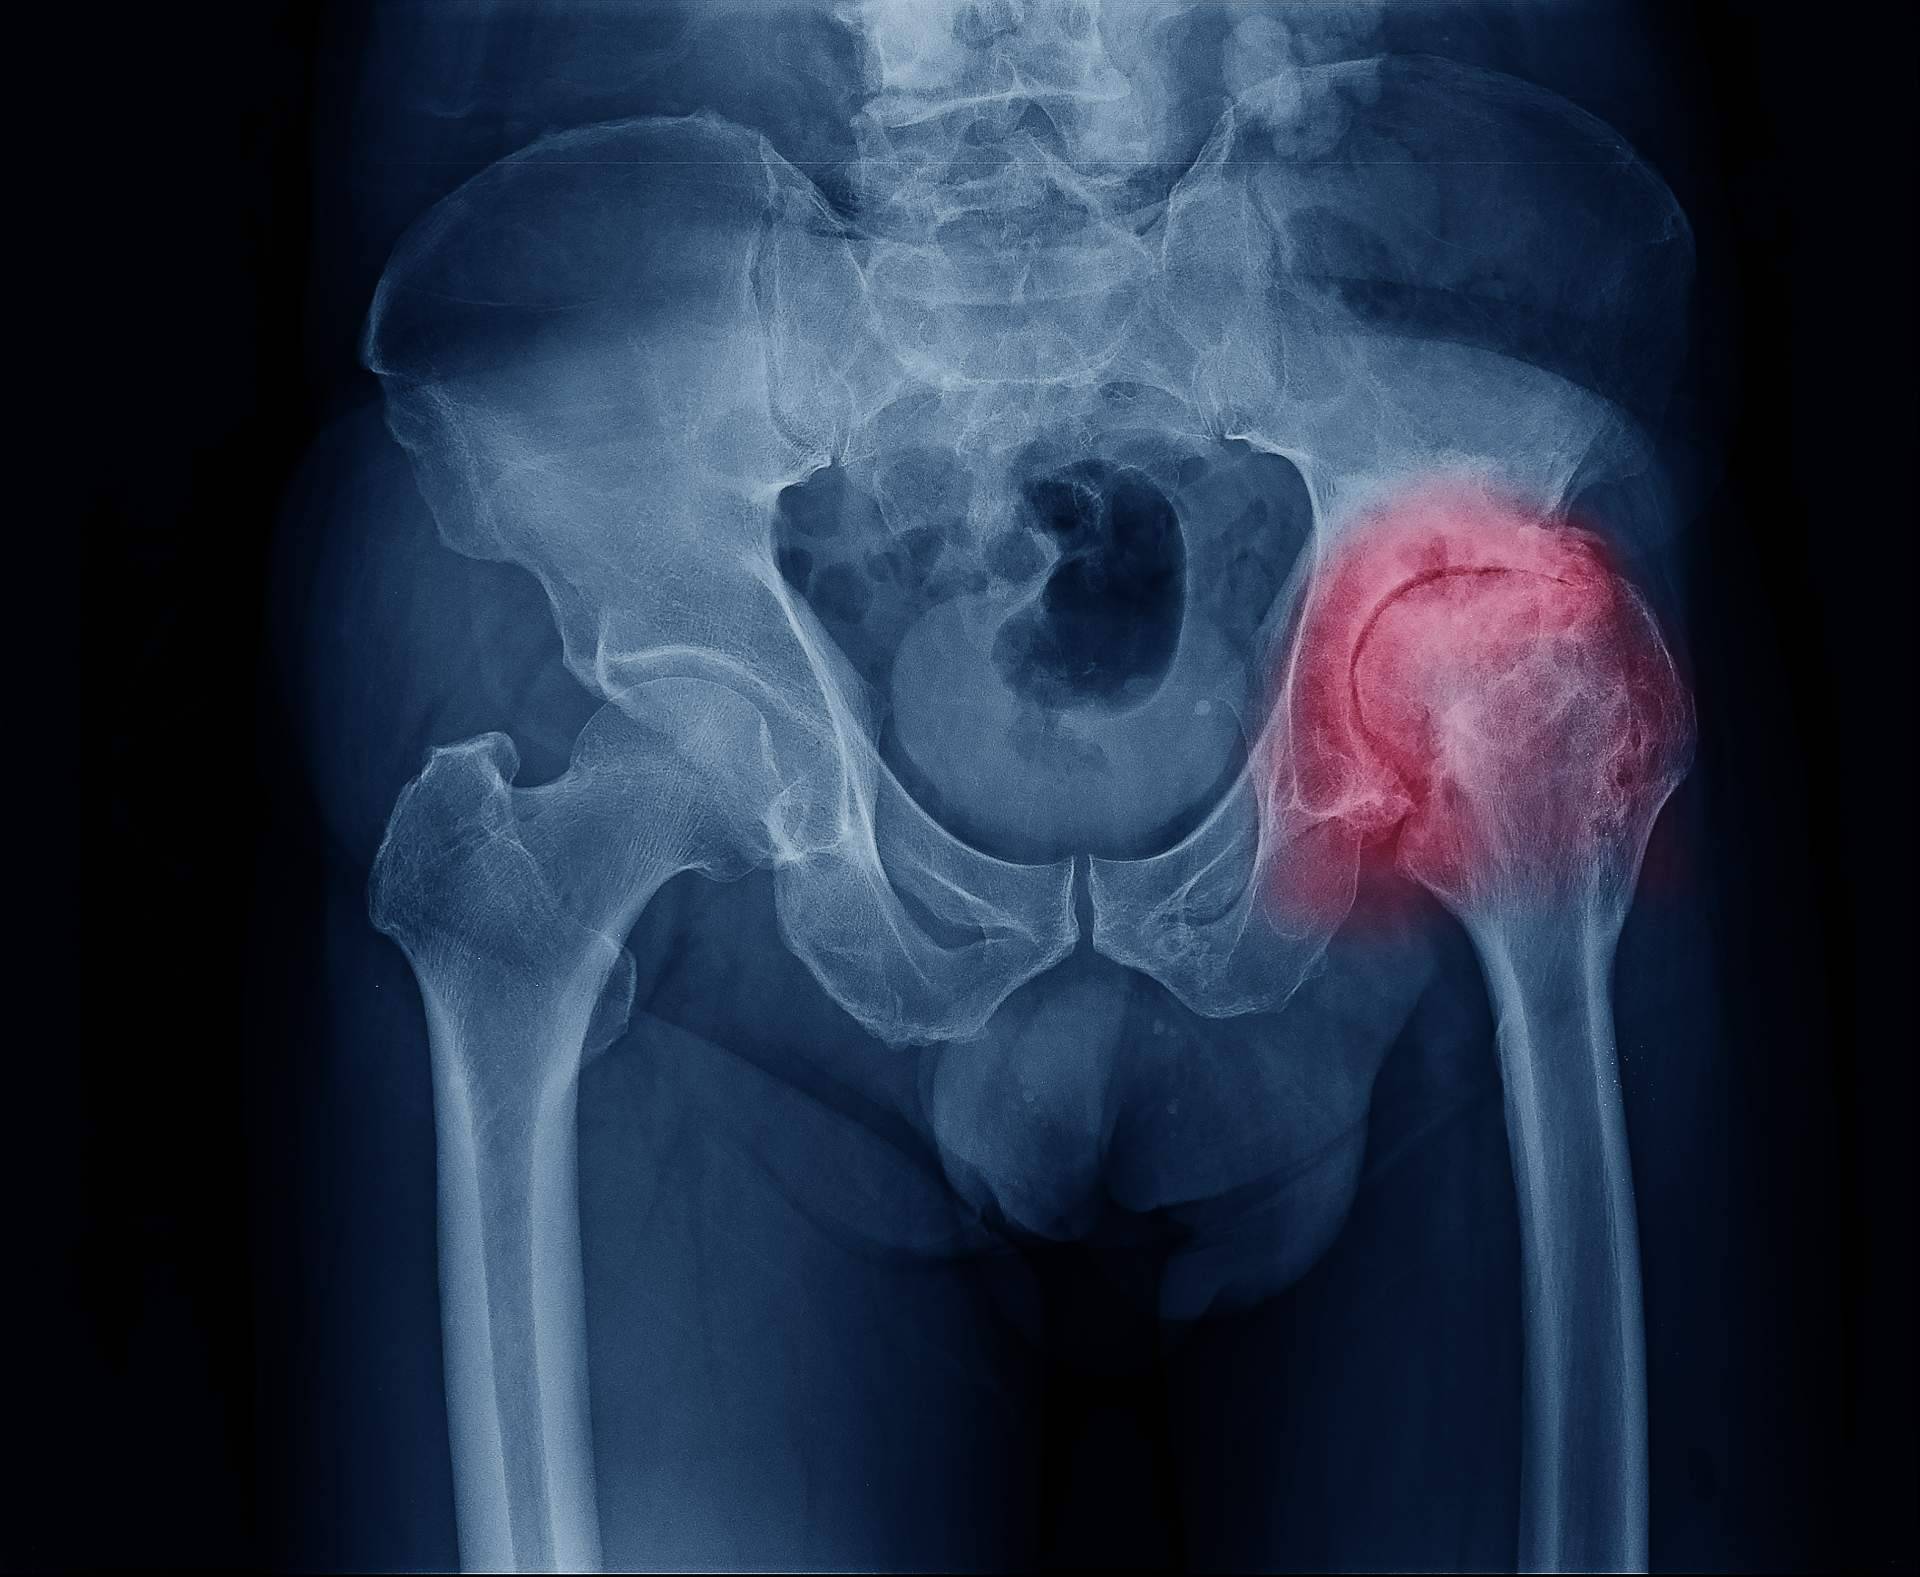

Según datos de la Organización Mundial de la Salud, la artrosis se ubica en el cuarto lugar de las enfermedades que menor calidad de vida otorga a sus pacientes año a año. La artrosis de cadera es uno de los tipos más comunes y afecta el cartílago que recubre la unión de los huesos de la pelvis y el fémur.

El síntoma fundamental que produce la artrosis de cadera es el dolor, el cual suele localizarse en la zona de la ingle, pudiéndose extender hacia la cara anterior del muslo, rodilla y nalga. El paciente suele presentar rigidez matutina y dificultad para caminar.